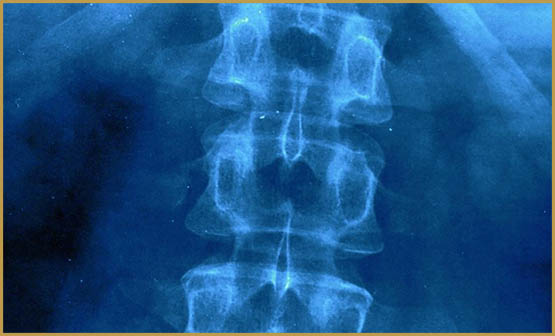

Un traumatisme médullaire correspond à un traumatisme au niveau de la moelle épinière. C’est à dire, la partie du système nerveux central qui permet la communication entre notre corps et notre cerveau. Ainsi, le traumatisme peut être causé par une chute, un accident ou d’un plongeon raté… Lors d’un accident grave le cannabis peut être employé après coup en tant qu’analgésique et stimulateur du système endocannabinoïde, qui a pour but de produire des cellules réparatrices

Selon la sévérité de la lésion, un traumatisme médullaire peut entraîner des troubles moteurs et sensitifs ainsi que des séquelles irréversibles (paralysie). La paraplégie désigne une paralysie des membres inférieurs (jambes). On parle de tétraplégie lorsque les bras et les jambes sont affectés.